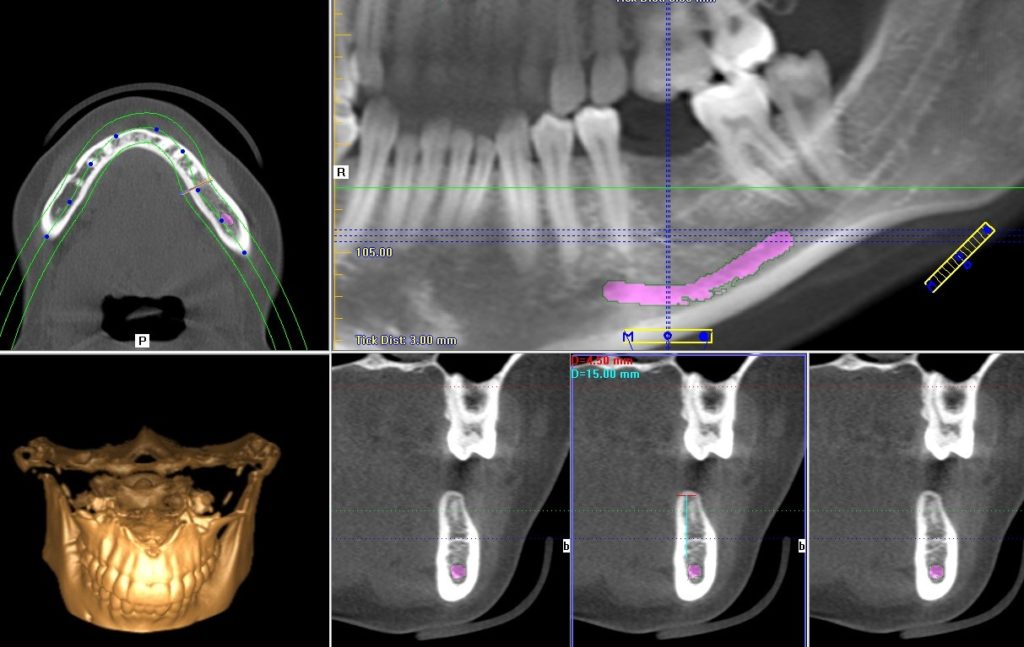

At the first appointment a CBCT (Cone beam computed tomography) scan was made in order to examine residual bone mass in 3 dimensions prior to implantation. Based on the CT scan it was established that the bone height and width were adequate for a thin but long implant to be installed. The stability of the implant was over 30 Ncm, allowing for a gingiva former to be installed that would see that the newly formed gumline perfectly suits the permanent abutment.

CT scan displaying the mandible ensuring a 3-dimensional examination of the bone height and bone width.